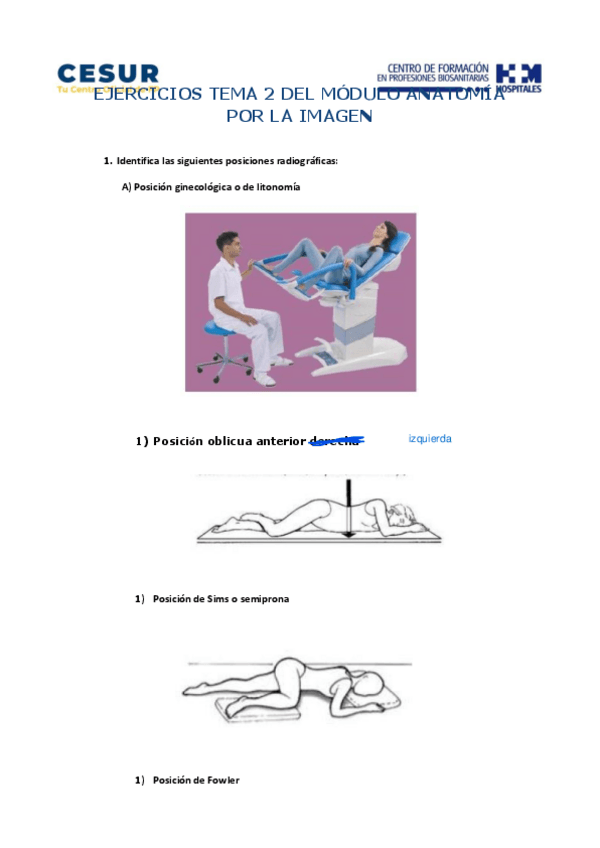

He publicado nuevos apuntes de Anatomía por la Imagen: Ejercicios-Tema-2-API-1-1.pdf